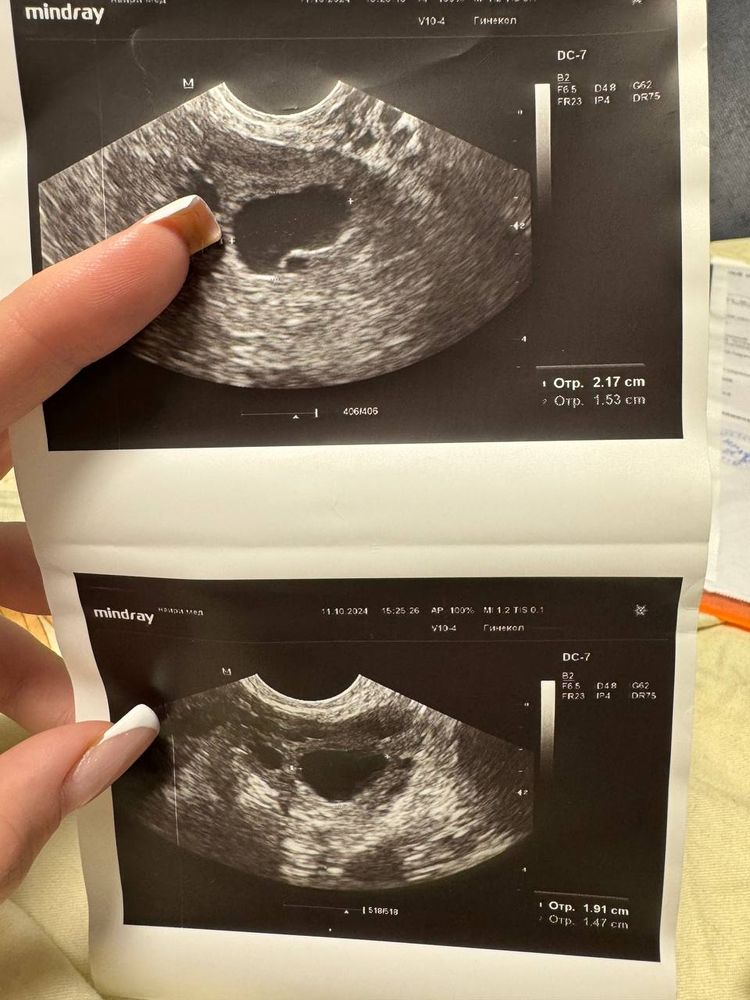

Была на узи перед биопсией 11.10.2024 - 22 день цикла, эндометрий 5,5, увидели слева «фолликул» 23 мм. (Месячные начались 17 числа, на 28 день цикла, но слабые и кровь была больше розовая - а были ли вообще это месячные?)

4.12.2024 я ходила на узи, там слева снова якобы «доминантный фолликул» 16,3 мм. При этом эндометрий 4,7.